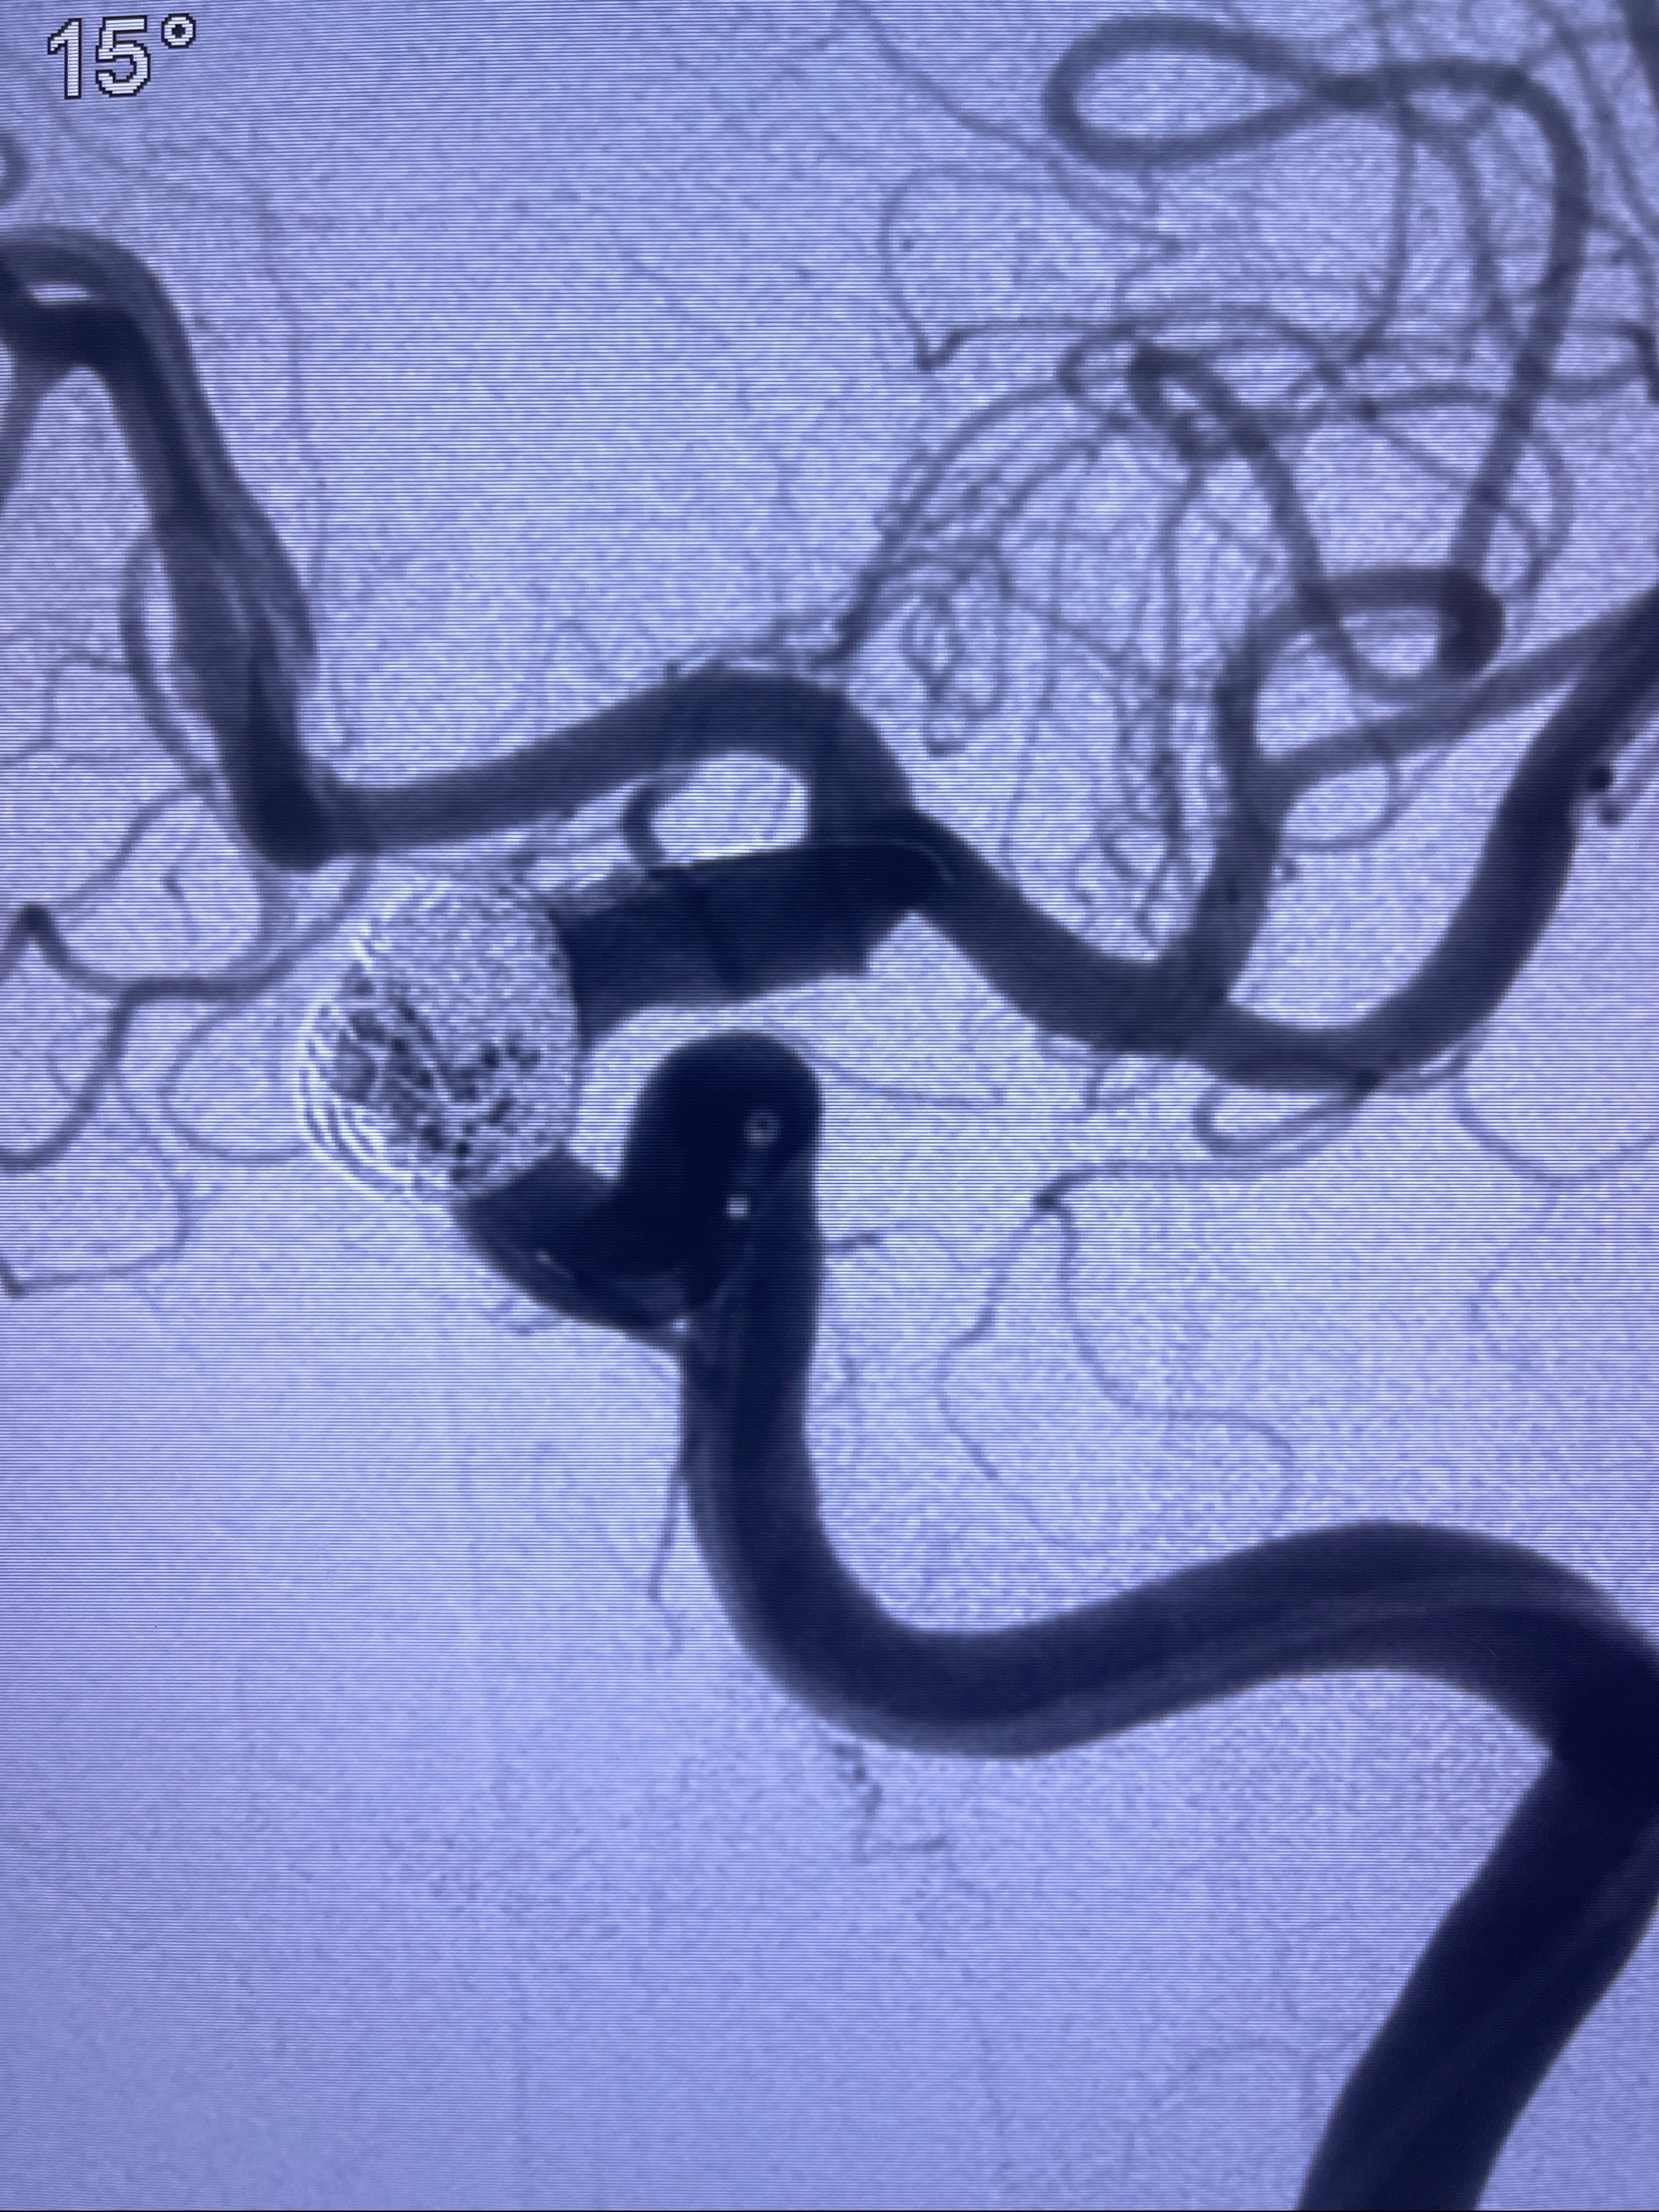

2023-09-06全麻下行左侧颈眼动脉瘤

密网支架辅助栓塞

- Tubridge 4.0-20mm密网支架

- 加奇微弹簧圈:7*30/6*20/5*20/2*8

术后3D显示支架贴壁佳